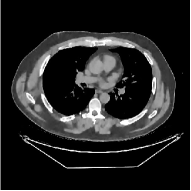

This section compares the reconstruction quality and runtime among the proposed MBIR method, PWLS-ST-, and other three MBIR methods, PWLS-EP, PWLS-DL, and PWLS-ST-. Table I shows that, for both 2D and 3D sparse-view CT reconstructions of the XCAT phantom, the proposed PWLS-ST- model outperforms PWLS-EP and PWLS-ST- in terms of RMSE. In addition, PWLS-ST- using a square transform (of size ) achieves lower RMSE than PWLS-DL using an overcomplete dictionary (of size ) for 2D sparse-view reconstructions. Fig. 3(a) and Fig. 4 show the reconstructed images for 2D and 3D phantom experiments, with different reconstruction models and different number of views. (See the corresponding error maps in the supplement.) The proposed PWLS-ST- consistently gives more accurate image reconstructions compared to other MBIR methods. Specifically, PWLS-ST- has smaller errors in the heart region (see zoom-ins in Fig. 3(a)) of 2D reconstructions than PWLS-DL and PWLS-ST-. In addition, compared to PWLS-ST-, PWLS-DL and PWLS-ST- have some ringing artifacts around the edges with high transition, e.g., edges between air and soft tissues. (See a comparison of profiles of PWLS-ST- and PWLS-ST- in the supplement.) In particular, PWLS-ST- and PWLS-DL give more visible ringing artifacts for 2D reconstruction from fewer views, and PWLS-ST- has these ringing artifacts for 3D reconstructions regardless of the number of views (see zoom-ins in Fig. 4). Table II reports runtimes of different MBIR methods in reconstructing the -views XCAT phantom scan. (FBPConvNet is a non-MBIR method and its runtime for processing a image is approximately one second with a TITAN Xp GPU.) While providing better reconstruction quality, the proposed Algorithm 1 of PWLS-ST- has shorter runtime compared to the algorithms of PWLS-DL and PWLS-ST- in Section III-A. Similar to the PWLS-EP algorithm, the reconstruction time of the PWLS-DL, PWLS-ST-, and PWLS-ST- algorithms can be further reduced by using ordered subsets [51].

![]() |

| (a) 2D fan-beam CT experiments |

| (b) 3D axial cone-beam CT experiments |